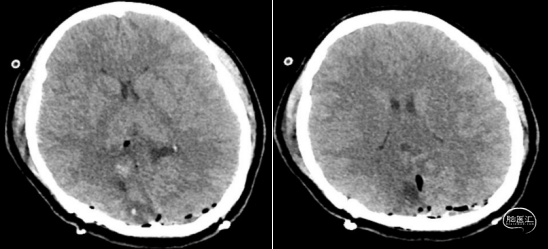

术后

术后管理要点:严密监测神经系统症状,密切观察患者头痛缓解情况、发热等。术中血性或者炎性脑脊液容易出现三脑室底、中脑导水管部分黏连或者堵塞形成梗阻性脑积水,需要定期复查,制定后续治疗综合方案,若仍不能缓解者则需要手术治疗。

本例患者影像学上表现为累及胼胝体压部的典型的蝴蝶状胶质瘤,病变累及双侧半球,非对称分布。手术均用右侧顶枕叶造瘘+左侧纵裂入路,术中先后探查和分块切除大脑镰后部两侧的病变。大脑镰后部毗邻大脑深部静脉系统,需要尽可能避免损伤Galen静脉或下矢状窦等重要结构,左侧纵裂入路可能有利于实现更好的功能保护。位于胼胝体不同部位的蝴蝶状肿瘤,由于解剖基础和功能保护的需求,采取不同的入路,从而在尽可能保护脑功能的前提下安全切除病变。